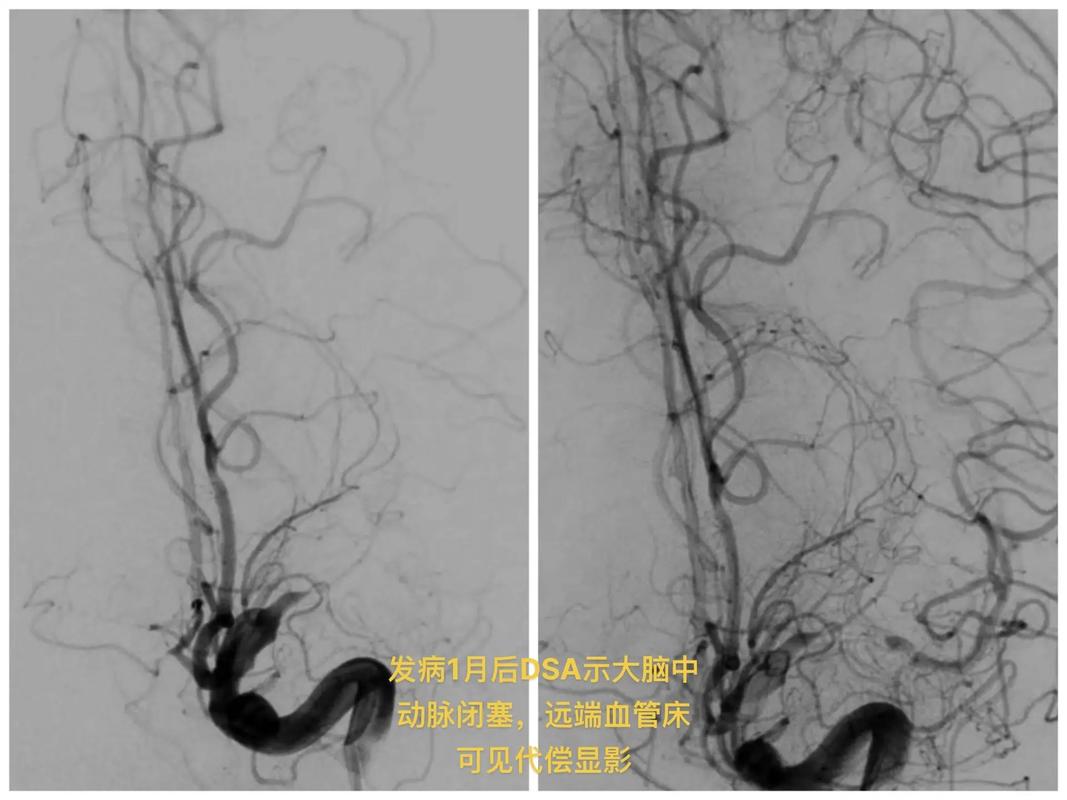

脑梗塞的发生:脱落的血栓会顺着主动脉向上流动,最终进入脑动脉,如果血栓的体积足够大,恰好卡在了某条较细的脑动脉里,就会完全堵住血管,导致该血管供应的大脑区域缺血、坏死,从而引发脑梗塞。